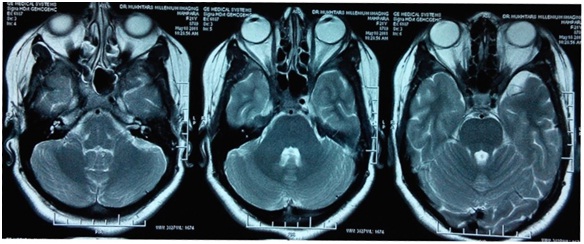

MRI SCAN OF ORBIT - JOMTONLINE.COM

Slice: 3 mm TR: 704 TE: 15 BRAIN Image no: 10 pos: HFS Image 19 of 28 4/17/2015, PM c: c: 97.0, 97.0, w: w: 168.5 168.5 1/7 Series: 1101 1/3 Slice: 2.5 mm ... Doc Retrieval